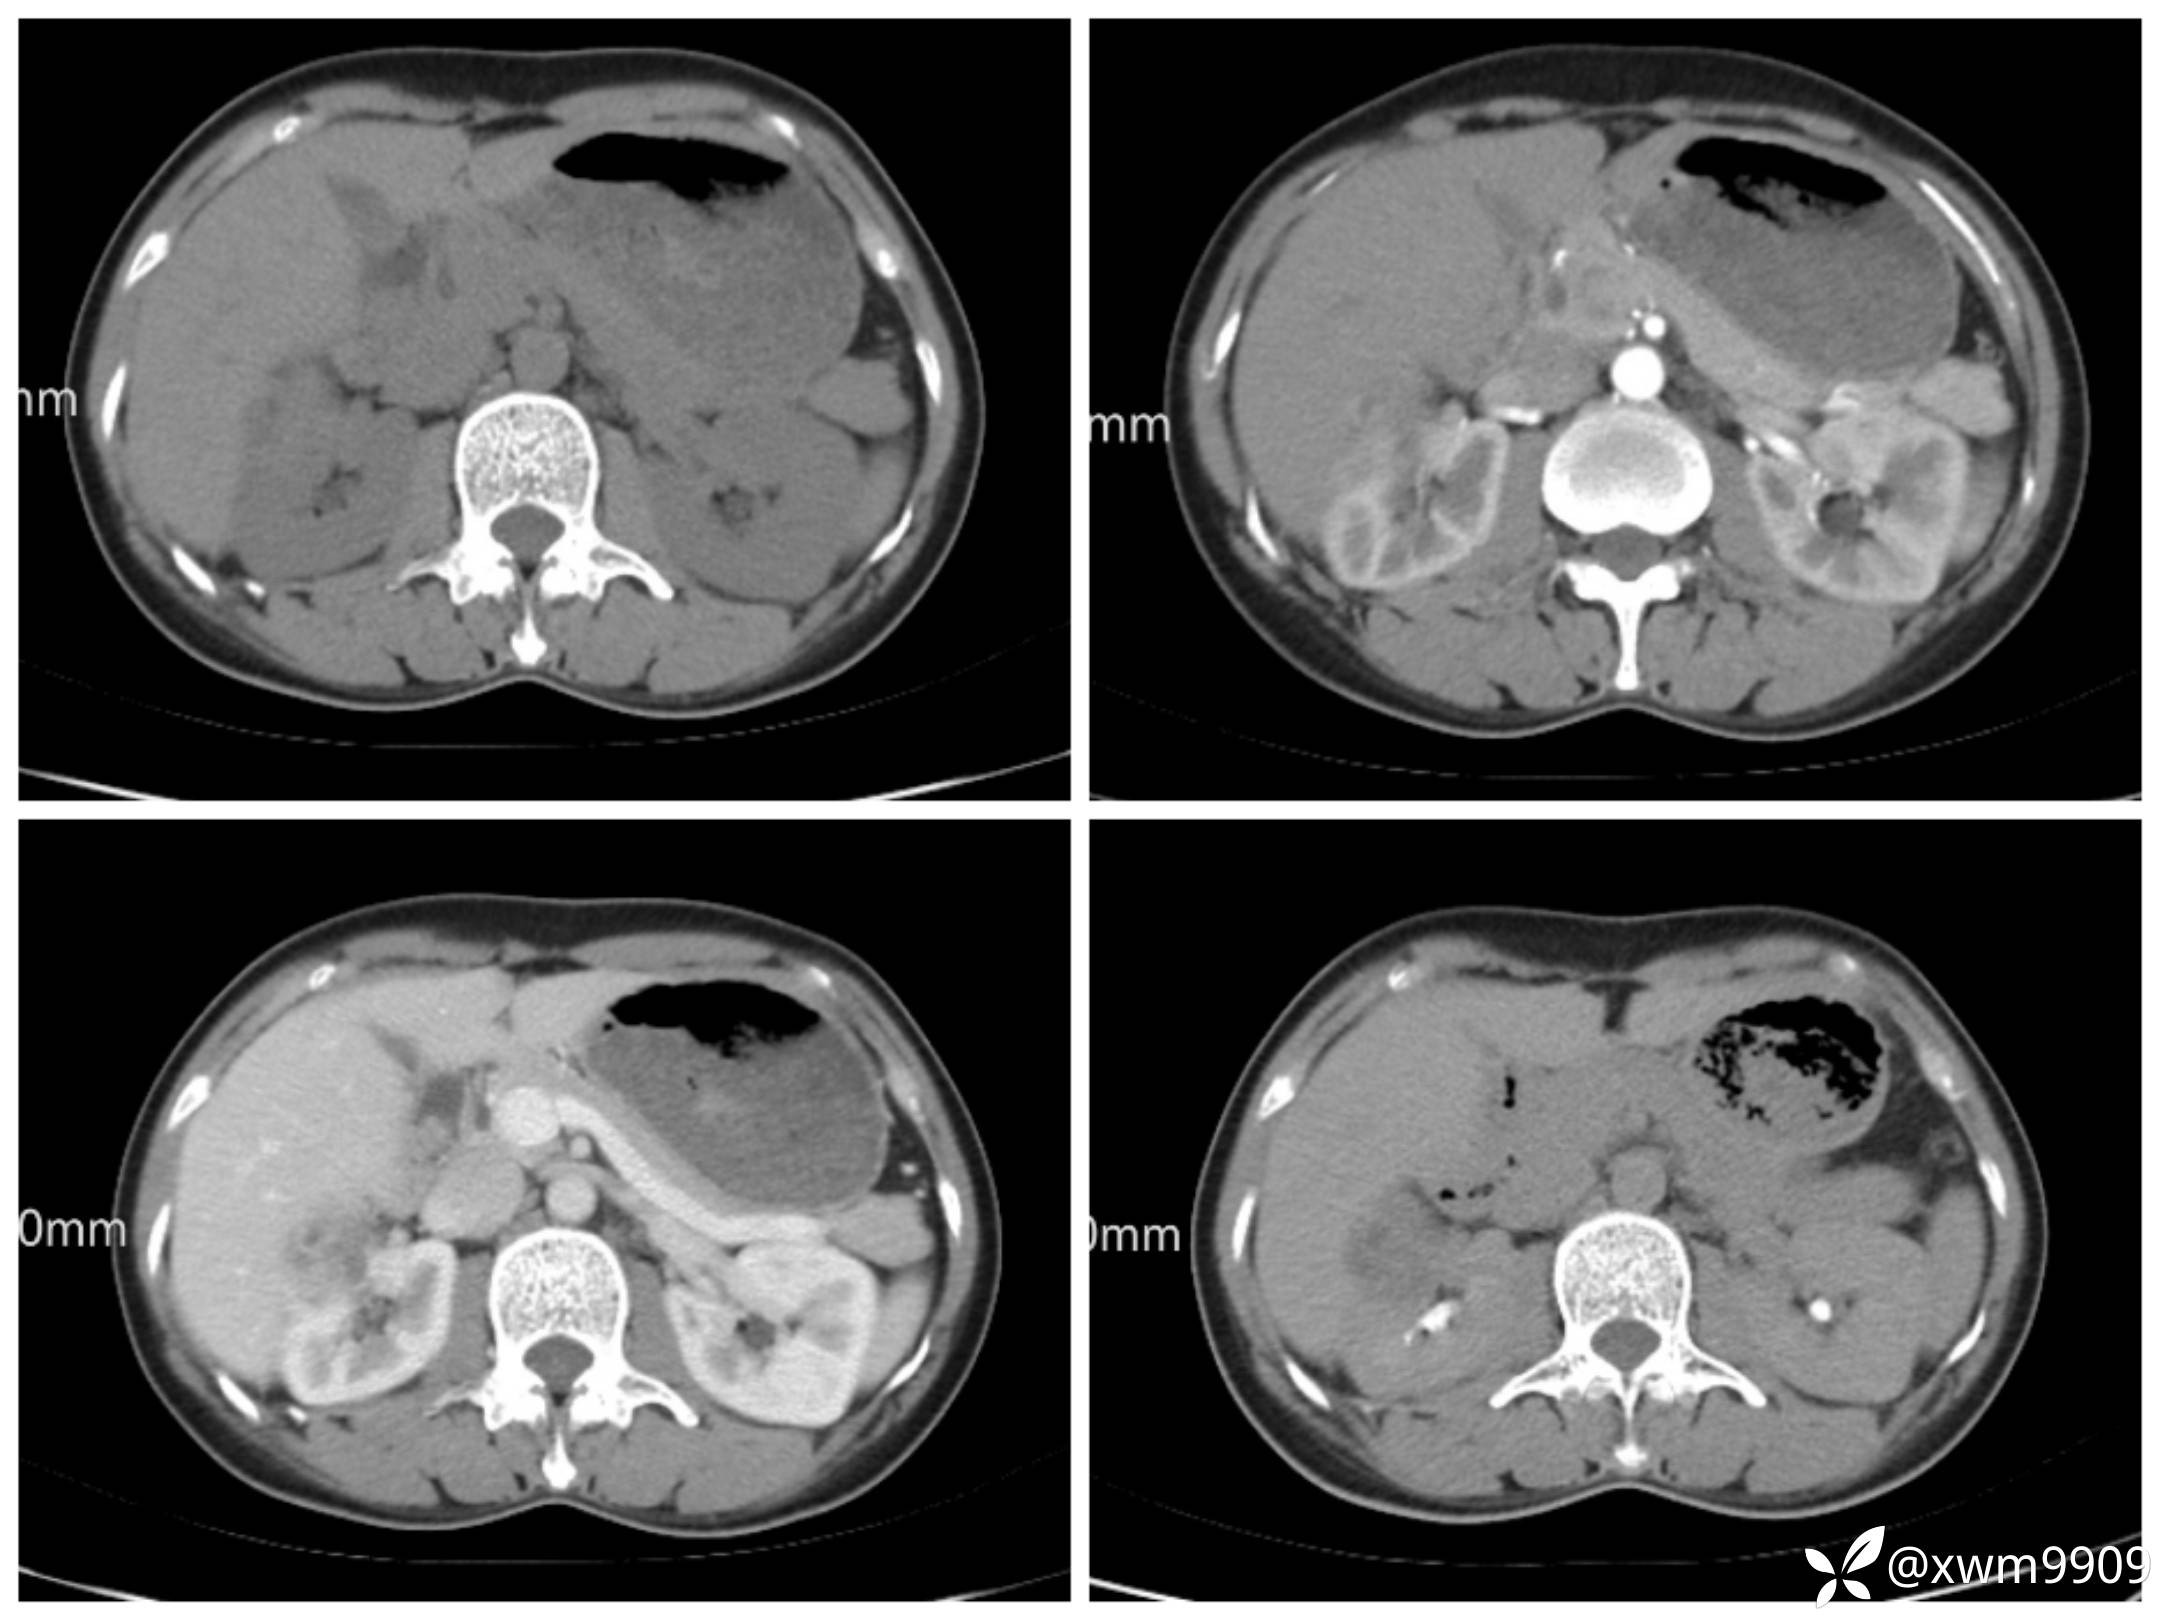

肾脏肿瘤知多少?请你慧诊!

hyy838 等 2 位达人已点赞主诉:体检发现右肾肿瘤1年。

1、入院症见:右侧腰部无明显胀痛,未见肉眼血尿,无尿频、尿急、尿痛,无恶寒、发热,无心慌、胸闷,无头晕、头痛,无腹痛、腹泻,纳寐可。大便正常,近期体重无明显变化。

2、专科检查:双肾区无畸形,双肾区无叩痛,双侧输尿管行程无压痛,膀胱区无隆起,无压痛,舌红、苔白腻、脉滑。

女性,41岁。